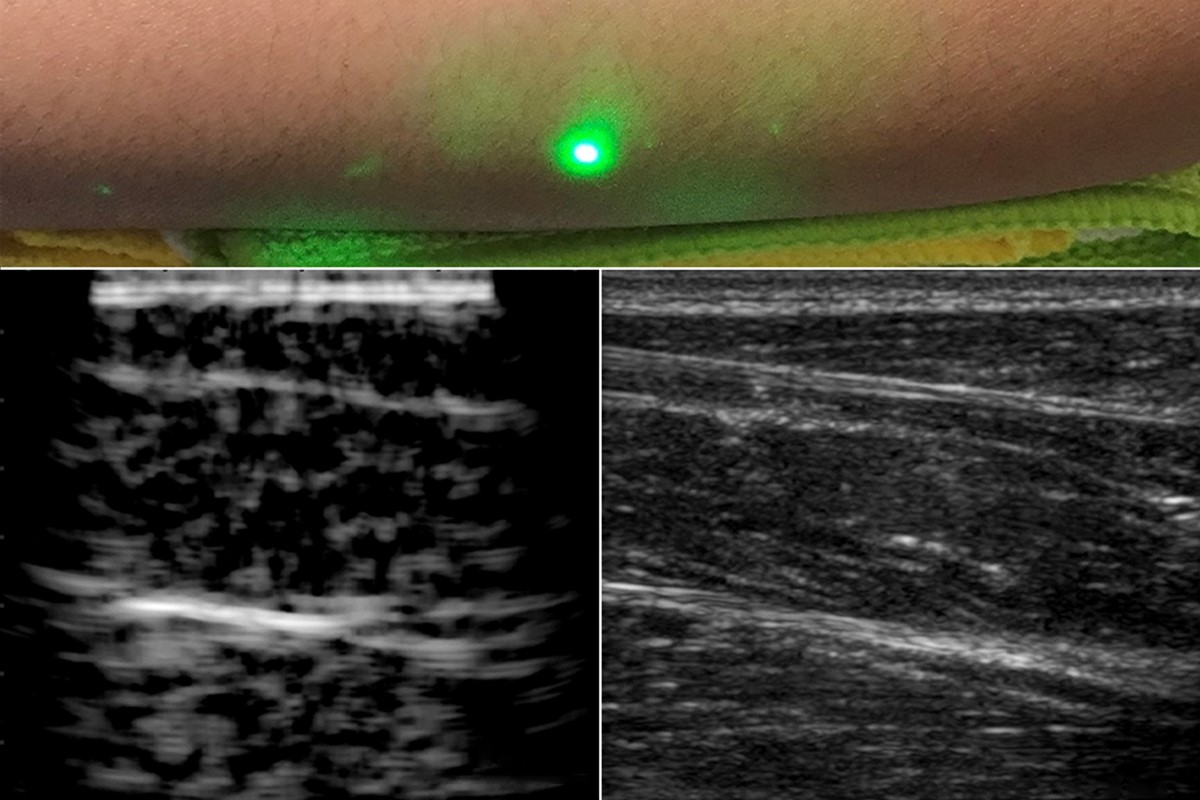

The researchers replaced the acoustic detector of conventional photoacoustic imaging with a 1550 nm continuous-wave laser-Doppler vibrometer to measure skin vibrations (see figure). This makes for a fully noncontact system, nearly eliminating the risk of repetitive-stress injuries for sonographers. The selection of wavelengths around 1550 nm allows the system to take advantage of advances in telecommunications technology, as well as matching tissue characteristics. In addition, the power and energy required by the LUS system are well within laser-exposure safety limits for human use.

The researchers validated their method on tissue phantoms with embedded metal features, porcine tissue, and human forearms, where the reconstructed images were consistent with traditional ultrasound images. The LUS images are comparable to circa-1960s ultrasound, prior to the electronics and manufacturing improvements that led to the rapid, high-quality imaging of contemporary ultrasound. Xiang (Shawn) Zhang, a researcher and author on the MIT team, noted that “early-stage ultrasound images were generated using a single transducer that was manually moved to generate an image, which is very similar to our present LUS, since we are moving laser spots on the skin surface. The system should benefit from an innovation pathway similar to that responsible for the past 50 years of traditional ultrasound development.” Advances in silicon photonics, for example, could lead to the development of multipoint light sources comparable to the piezoelectric arrays of traditional ultrasound.